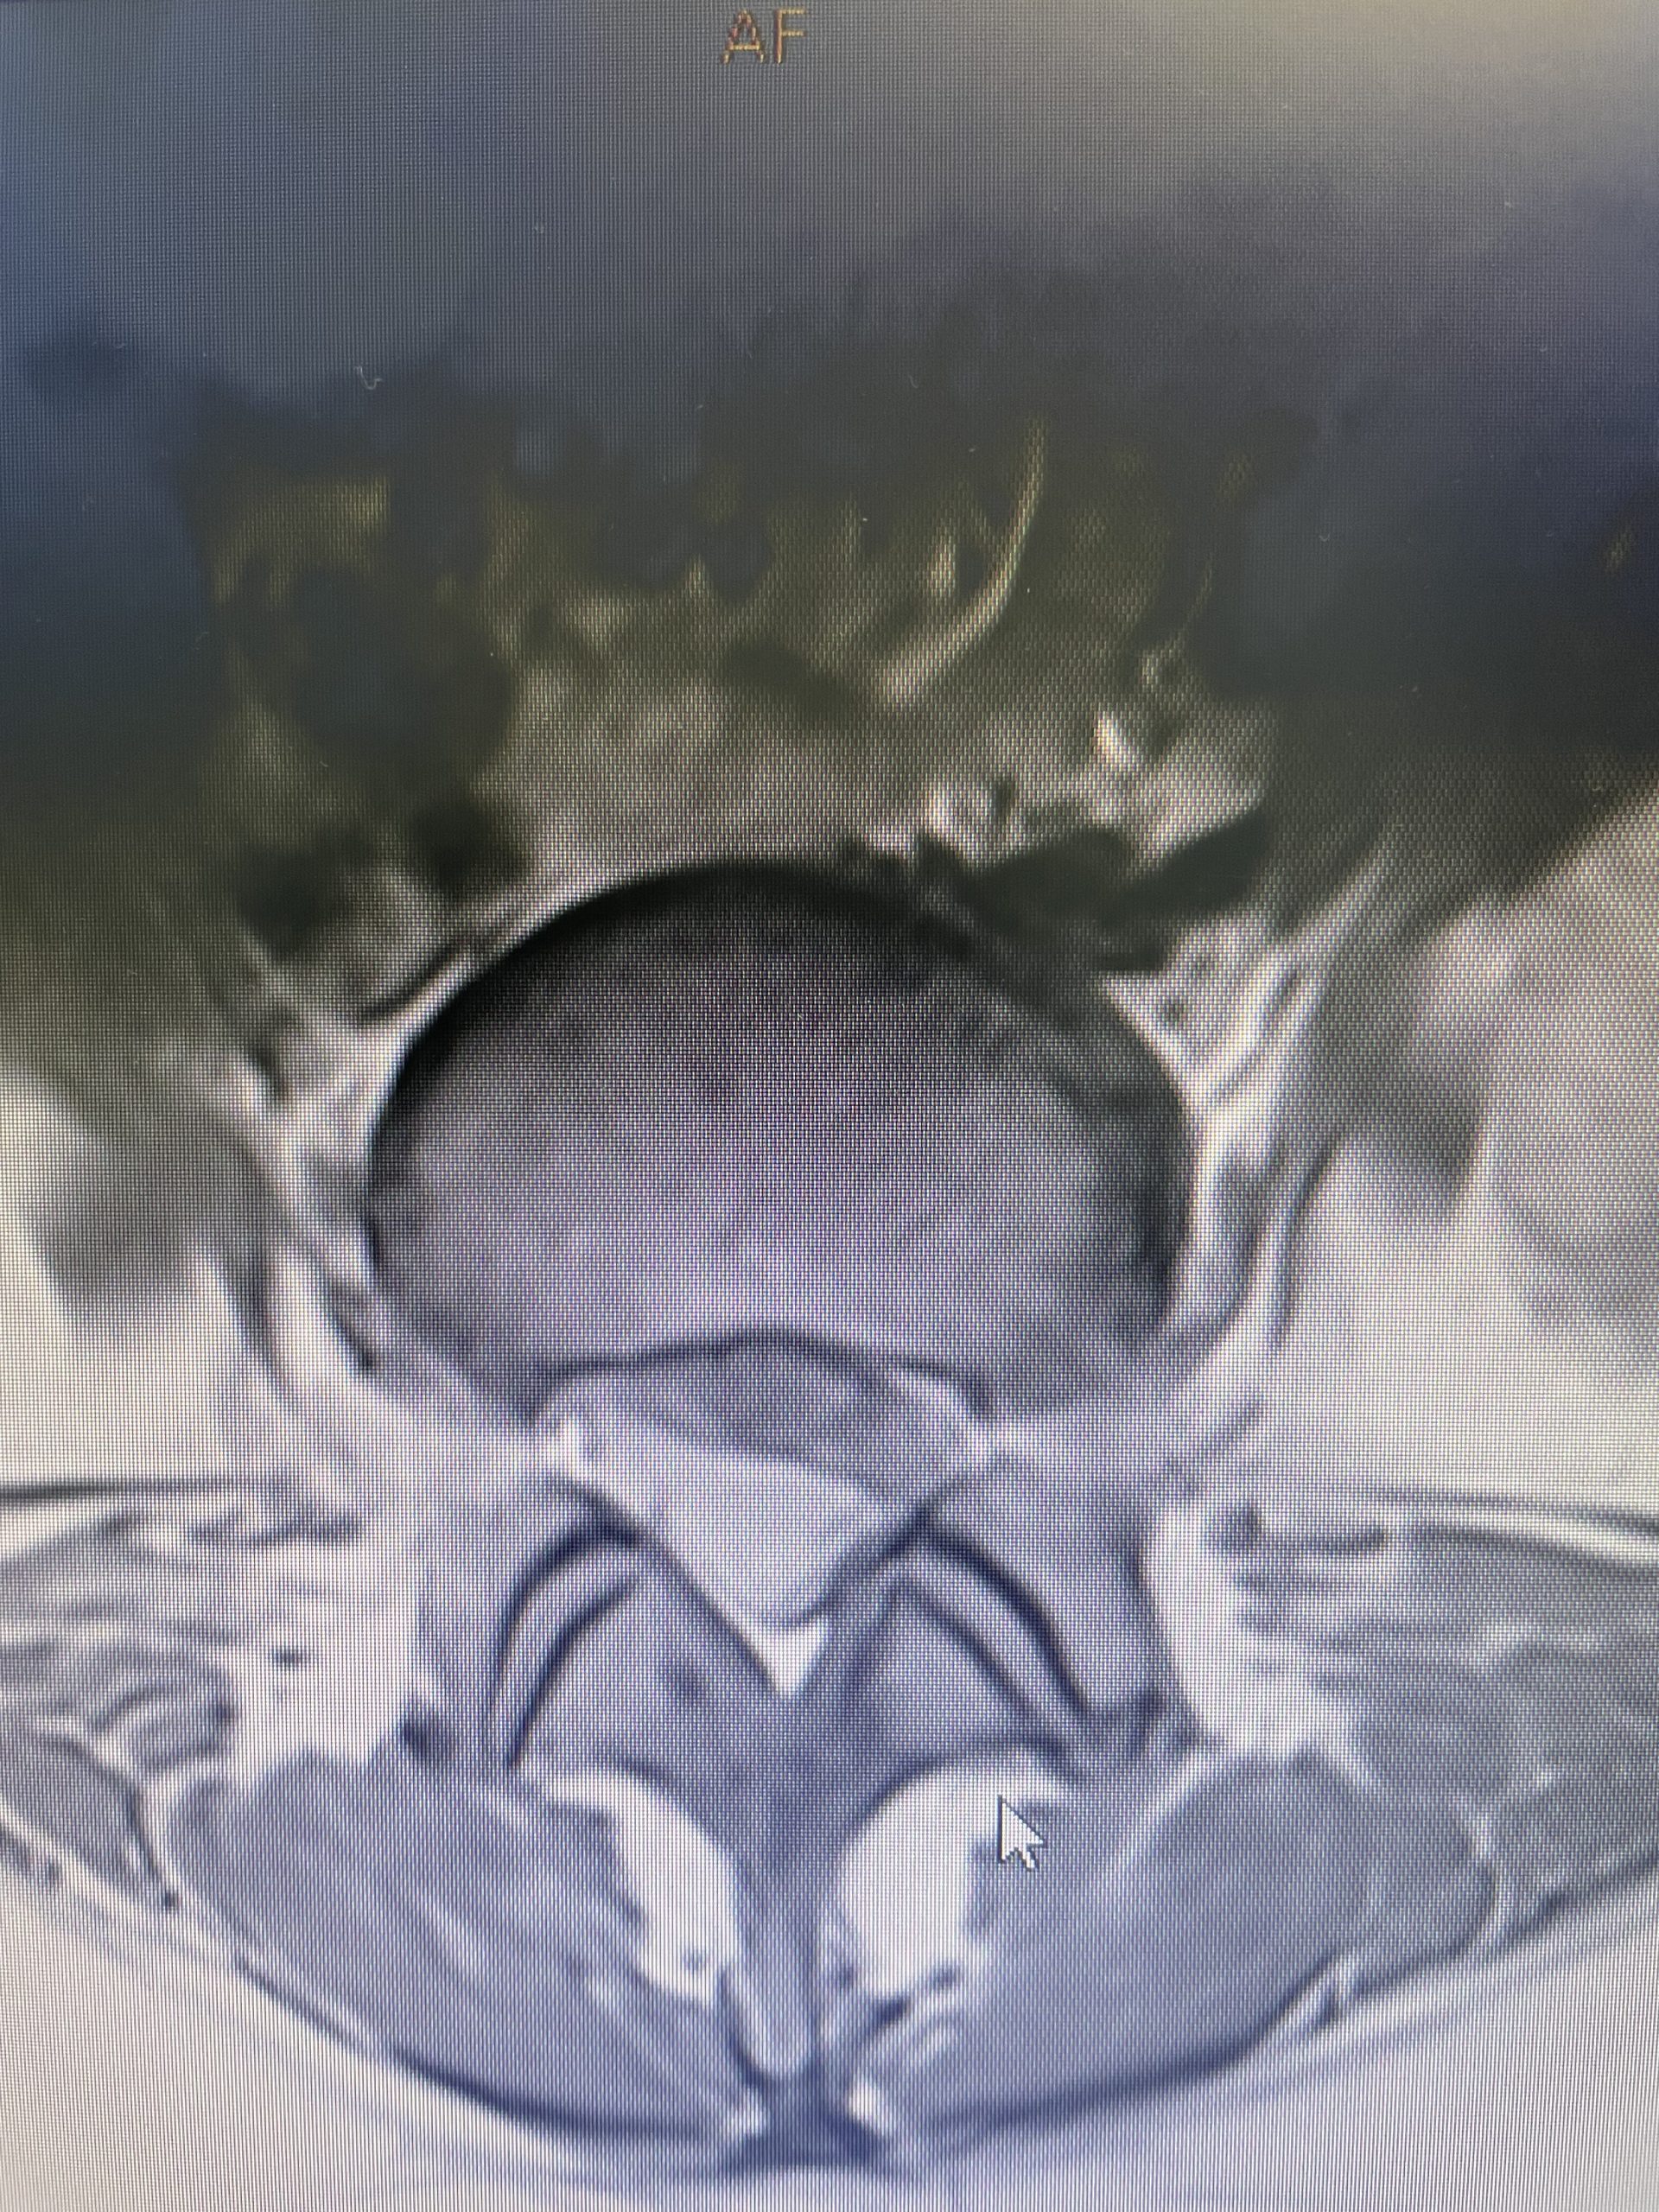

This 42-year-old female presents with ten years of progressive low back pain and leg pain. She had mild left dorsiflexion and EHL weakness. She had tried physical therapy, but her symptoms persisted. MRI revealed an L4-5 grade 1 spondylolisthesis with stenosis (Fig 1). We discussed options. We decided to try an epidural injection and continue with physical therapy. She will follow up with me in 6-8 weeks to see how she is doing with her pain and strength.